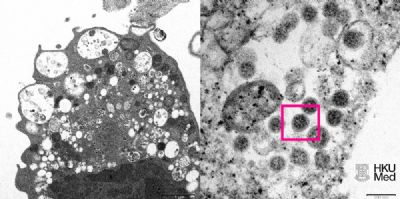

A variante ômicron – também chamada B.1.1529 – foi reportada à Organização Mundial da Saúde (OMS) em 24 de novembro de 2021 pela África do Sul.

O primeiro caso confirmado da B.1.1529 foi de uma amostra coletada em 9 de novembro de 2021. De acordo com OMS, a variante apresenta um “grande número de mutações”, algumas preocupantes.

“Evidências preliminares sugerem uma alta no risco de reinfecção com a variante, comparada com as outras versões do coronavírus”, disse a agência de Saúde das Nações Unidas em um comunicado.